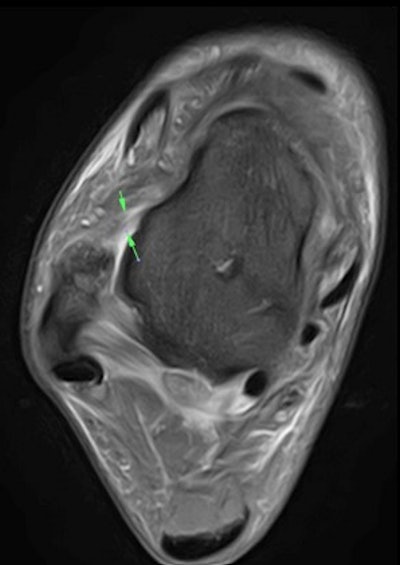

Axial fat-suppressed proton density 3-tesla MRI of the right ankle demonstrates a grade 1/2 tear of the anterior talofibular ligament (ATFL).ACL injuries happen suddenly and without warning and can mean being out of the game for between nine and 12 months. These injuries are common in football due to the frequent and instant deceleration on the pitch from cutting, pivoting, or landing on one leg.

By using a Canon Medical Vantage Galan 3-tesla MRI scanner, we can see the extent of commonly occurring or unique injury onsite within the dedicated Medical Imaging Centre at the Manchester United Carrington Training Centre without any of the confidentiality issues of transferring a patient to a local hospital.